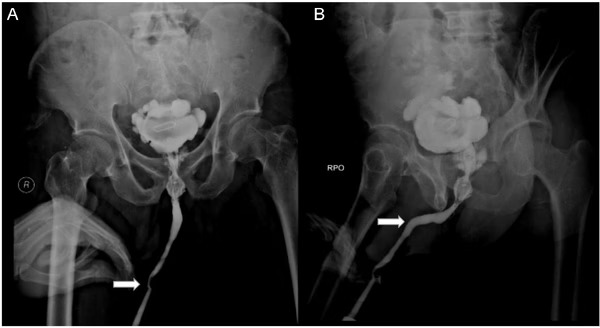

A radiografia revelou objetos estranhos, incluindo uma pedra na bexiga causada pelo objeto de metal. Durante a cirurgia, os médicos removeram uma pedra de 5×3 cm, além do cabo elétrico e uma agulha de 8 cm.

Exames posteriores mostraram complicações no ureter, com o paciente desenvolvendo hidronefrose. Os psiquiatras diagnosticaram um transtorno de adaptação, mas a causa não foi esclarecida.